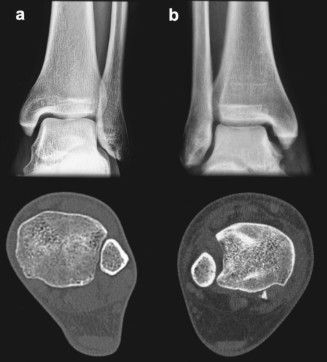

A Tomografia Computadorizada com Carga Simulada:

Este exame é uma ferramenta diagnóstica revolucionária e de extrema importância para definir a conduta em lesões da sindesmose.

Como funciona:

O exame é realizado com o paciente apoiando peso ou sob uma carga controlada no tornozelo, simulando a pressão que a articulação sofreria durante atividades diárias.

Por que é crucial:

- Revela Instabilidade Oculta: Muitas vezes, uma sindesmose pode parecer estável em exames de imagem feitos em repouso. A carga simulada "desmascara" a instabilidade, mostrando um alargamento anormal da pinça tibiofibular que não seria visível de outra forma.

- Guia a Decisão Cirúrgica: Ao identificar essa instabilidade dinâmica, o exame ajuda o ortopedista a determinar se o tratamento cirúrgico é necessário, mesmo em casos que, à primeira vista, pareceriam menos graves.

- Otimiza o Tratamento: Com um diagnóstico mais preciso da instabilidade real, o Dr. Felipe Serzedello pode planejar a intervenção mais adequada, garantindo melhores resultados e uma recuperação mais eficaz para o paciente.